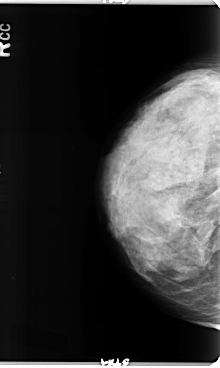

B_3358_1.RIGHT_CC

RIGHT_CC LINES 4784 PIXELS_PER_LINE 2848 BITS_PER_PIXEL 12 RESOLUTION 50 NON_OVERLAY

FILE: B_3358_1.LEFT_CC.OVERLAY

TOTAL_ABNORMALITIES 1

ABNORMALITY 1

LESION_TYPE CALCIFICATION TYPE ROUND_AND_REGULAR-PUNCTATE-AMORPHOUS DISTRIBUTION REGIONAL

ASSESSMENT 3

SUBTLETY 3

PATHOLOGY BENIGN

TOTAL_OUTLINES 1

BOUNDARY